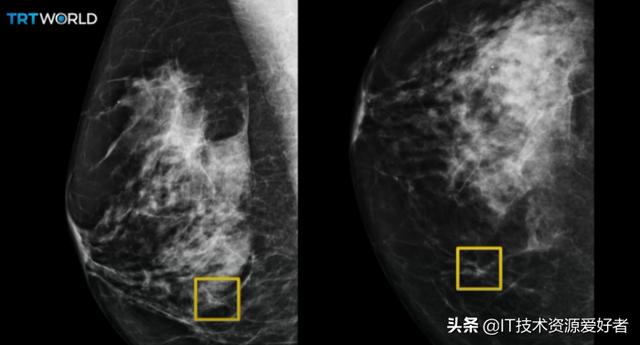

谷歌健康的 AI 能比专家更准确的检查出乳房癌症。

英国每一年都有超过 55000 人被诊断出乳腺癌,而美国那边每 8 名妇女就会有 1 人在有生之年患上乳腺癌。

关键是多数的乳腺癌症状在前期表现都不明显,很容易被忽视或者没有及时被筛查出来。

而谷歌去年一月发表在《 Nature 》的一篇文章,分享了 AI 是如何准确识别女性乳腺癌的早期迹象。

谷歌联合 DeepMind 、英国癌症研究中心、西北大学,采集了来自英国 76000 多名、美国 15000 多名女性的 X 光检查数据。

基于这些数据训练出来的 AI 模型,检查了英国 25000 多名和美国 3000 多名的 X 光检查样片。

相较于人工筛查, AI 在美国减少了 5.7% 的乳腺癌误报,在英国减少了 1.2% 。

仅通过观察 X 射线实片来对乳腺癌进行筛查,这个 AI 模型在识别乳腺癌的准确率方面早就超过了部分专家。